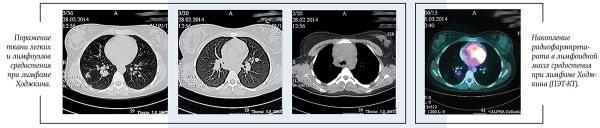

В настоящее время стандартом обследования при ЛХ является позитронно-эмиссионная томография с 18F-флюородезокси-глюкозой, совмещенная с КТ (ПЭТ-КТ).

ПЭТ-КТ позволяет точнее определить вовлеченные в опухолевый процесс лимфатические узлы и области организма, определить стадию и объем лечения. В нашей стране данный метод стал доступен для всех пациентов с ЛХ с 2017 года.

ПЭТ-КТ: в переднем средостении верхнего этажа срединно с акцентом вправо опухолевая масса; 36ґ73ґ60 мм. Изолированно лежащие увеличенные лимфоузлы: паратрахеальные и бифуркационные, до 15 мм; парастернально справа, до 18 мм. По данным ПЭТ: накопление РФП помимо вышеописанных узлов — в правом корне (бронхопульмональные л/узлы), в л/узлах — прекардиально справа, в кардиодиафрагмальной области слева, параэзофагеально (на КТ узел, 14 мм).

Очагов патологической плотности в легочной паренхиме не выявлено. Легочной рисунок не изменен. Долевые и сегментарные бронхи проходимы. Корни легких не расширены, структурны. Подмышечные л/узлы не увеличены. Плевральные полости свободны. Мягкие и костные ткани грудной клетки без структурных изменений. Отмечается увеличение забрюшинных л/узлов, до 23 мм; общих подвздошных до 15 мм. На ПЭТ патологическое накопление РФП помимо вышеописанных узлов — в воротах печени, в наружных подвздошных л/узлах, в селезенке.

В левой подвздошной кости определяется очаг гиперденсивной плотности с мелкобугристыми контурами, размером 10,5ґ6,6 мм. На ПЭТ также отмечается повышенное накопление РФП в телах позвонков С6, Тн4, L5, S1; ребрах; костях таза.

Получен полный метаболический ответ по данным ПЭТ-КТ после этапа ПХТ. С целью консолидации ремиссии проведена лучевая терапия на зоны инициального поражения в СОД=20 Гр.